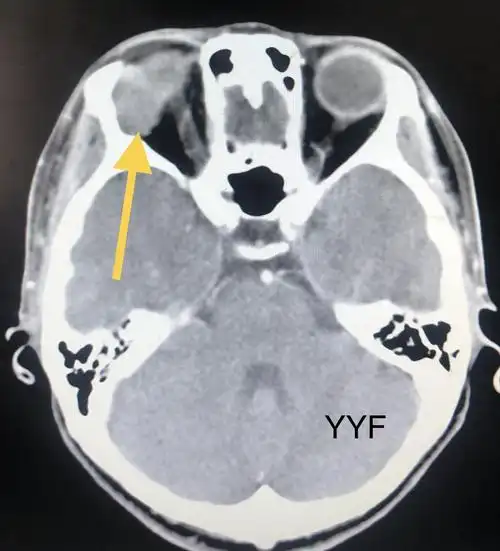

结节性腮腺混合瘤